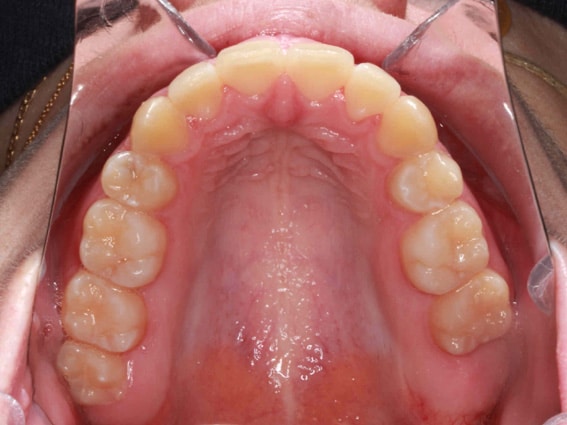

Une fois le traitement abouti, les objectifs fixés ont été atteints, point par point :

1. Des espaces d’extraction totalement refermés

Aucun espace n’est réapparu, même après plusieurs mois. La fermeture est stable et définitive.

2. Correction de la protrusion des dents du haut

Les incisives supérieures ont retrouvé une position naturelle : elles ne sont plus projetées vers l’avant.

3. Alignement optimisé pour l’arcade supérieure

4. Ligne médiane corrigée, sourire rééquilibré

Pour maintenir le résultat, nous avons prescrit une contention amovible pour la nuit sur la mâchoire supérieure, et une combinaison de fil de contention fixe et de gouttière nocturne pour l’arcade inférieure.